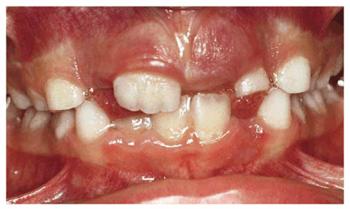

A female patient, 6 years, 7 months old.

PROBLEM: The patient's frontal view showed a serious bimaxillary

crowding with deviation of the midline. When teeth #7 and #10 erupted, crowding

problems greatly increased. Also, tooth #10 was in crossbite (Figure 27-9A).

Figure 27-9A: A serious bimaxillary crowding with deviation of the midline in a 6-year, 7-month-old female.

TREATMENT: After a

short observation period, while the lateral incisors erupted, the pediatric

dentist and the orthodontist initiated therapy. M and R were sliced, and a lip

bumper was applied to K and T. The occlusal surface rose to resolve the

crossbite of the upper left lateral incisor. The maxillary arch was treated orthodontically

to correct the alignment (Figure 27-9B).

Figure 27-9B: After a short observation period, the early orthodontic therapy is started.

RESULT: The patient underwent an early orthodontic treatment for 1 year

that achieved arch balance, improvement of esthetics, and health of the oral

tissues. Furthermore, the improved smile contributed to greater self-confidence

and an improved sense of well-being (Figures 27-9C and D).

Figure 27-9C and D: The patient's smile and the lower arch after the orthodontic treatment: good balance and esthetics are achieved.